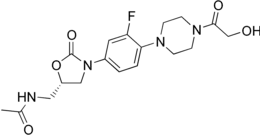

| Formula | C18H23FN4O5 |

| Molar mass | 394.40 g·mol−1 |

Eperezolid is an oxazolidinone antibiotic.

Eperezolid synthesis [1]